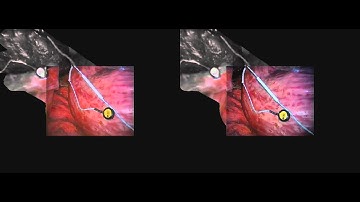

Download lagu Dense Surface Reconstruction for Enhanced Navigation in Minimally Invasive Surgery secara gratis hanya untuk keperluan promosi. Dukung artis favorit kamu dengan membeli musik original di iTunes atau platform resmi lainnya.